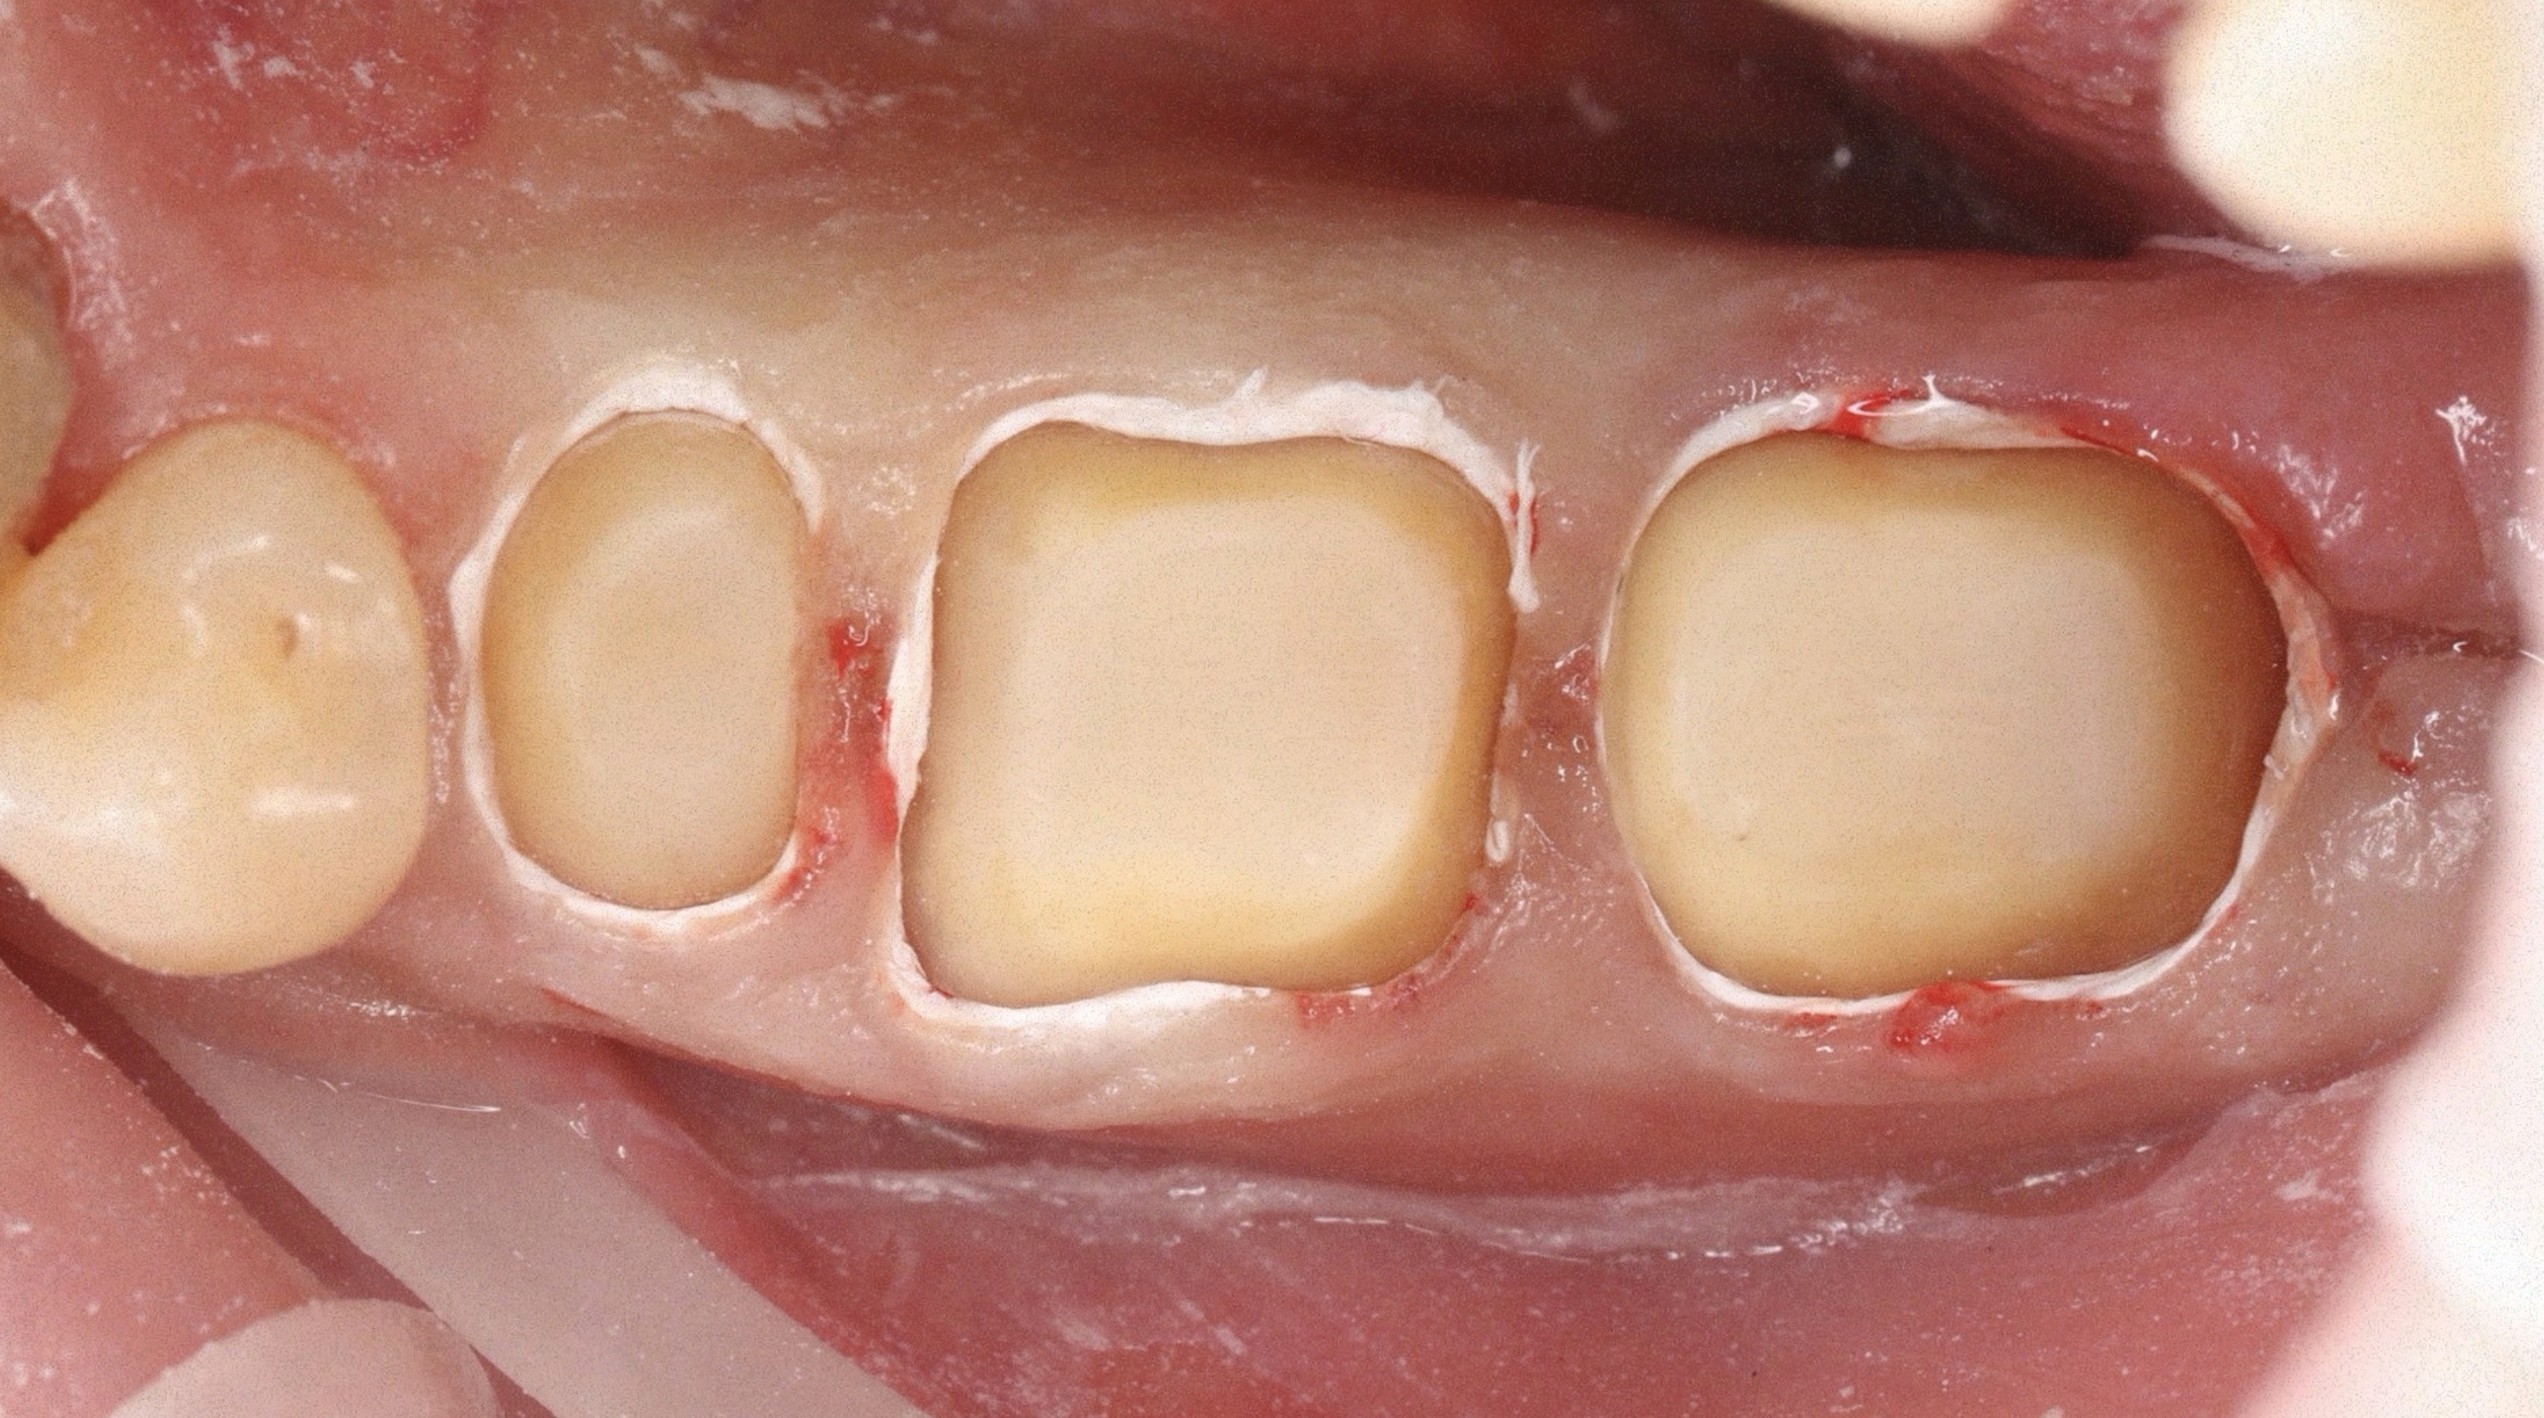

Все про препарування з уступом та без нього

Все про вертикальне препарування та преп з уступом. Чіткі клінічні протоколи

Препарування з уступом та без нього

Як препарувати зуби мінімально інвазивно для максимального їх збереження

Максимальне збереження зубів